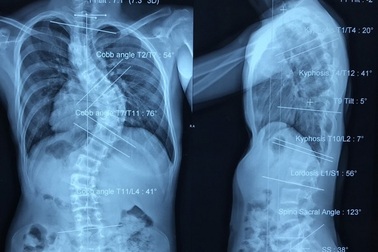

Nam thanh niên có cột sống uốn lượn như… xương rắnNhập viện trong tình trạng vai lệch, ngực lõm, khó thở… trên phim X-quang bác sĩ phát hiện xương cột sống của bệnh nhân bị vẹo nặng. Bằng phương pháp đặt nẹp vít, các bác sĩ đã nắn thẳng cột sống, giúp bệnh nhân thoát khỏi nguy cơ yếu liệt.